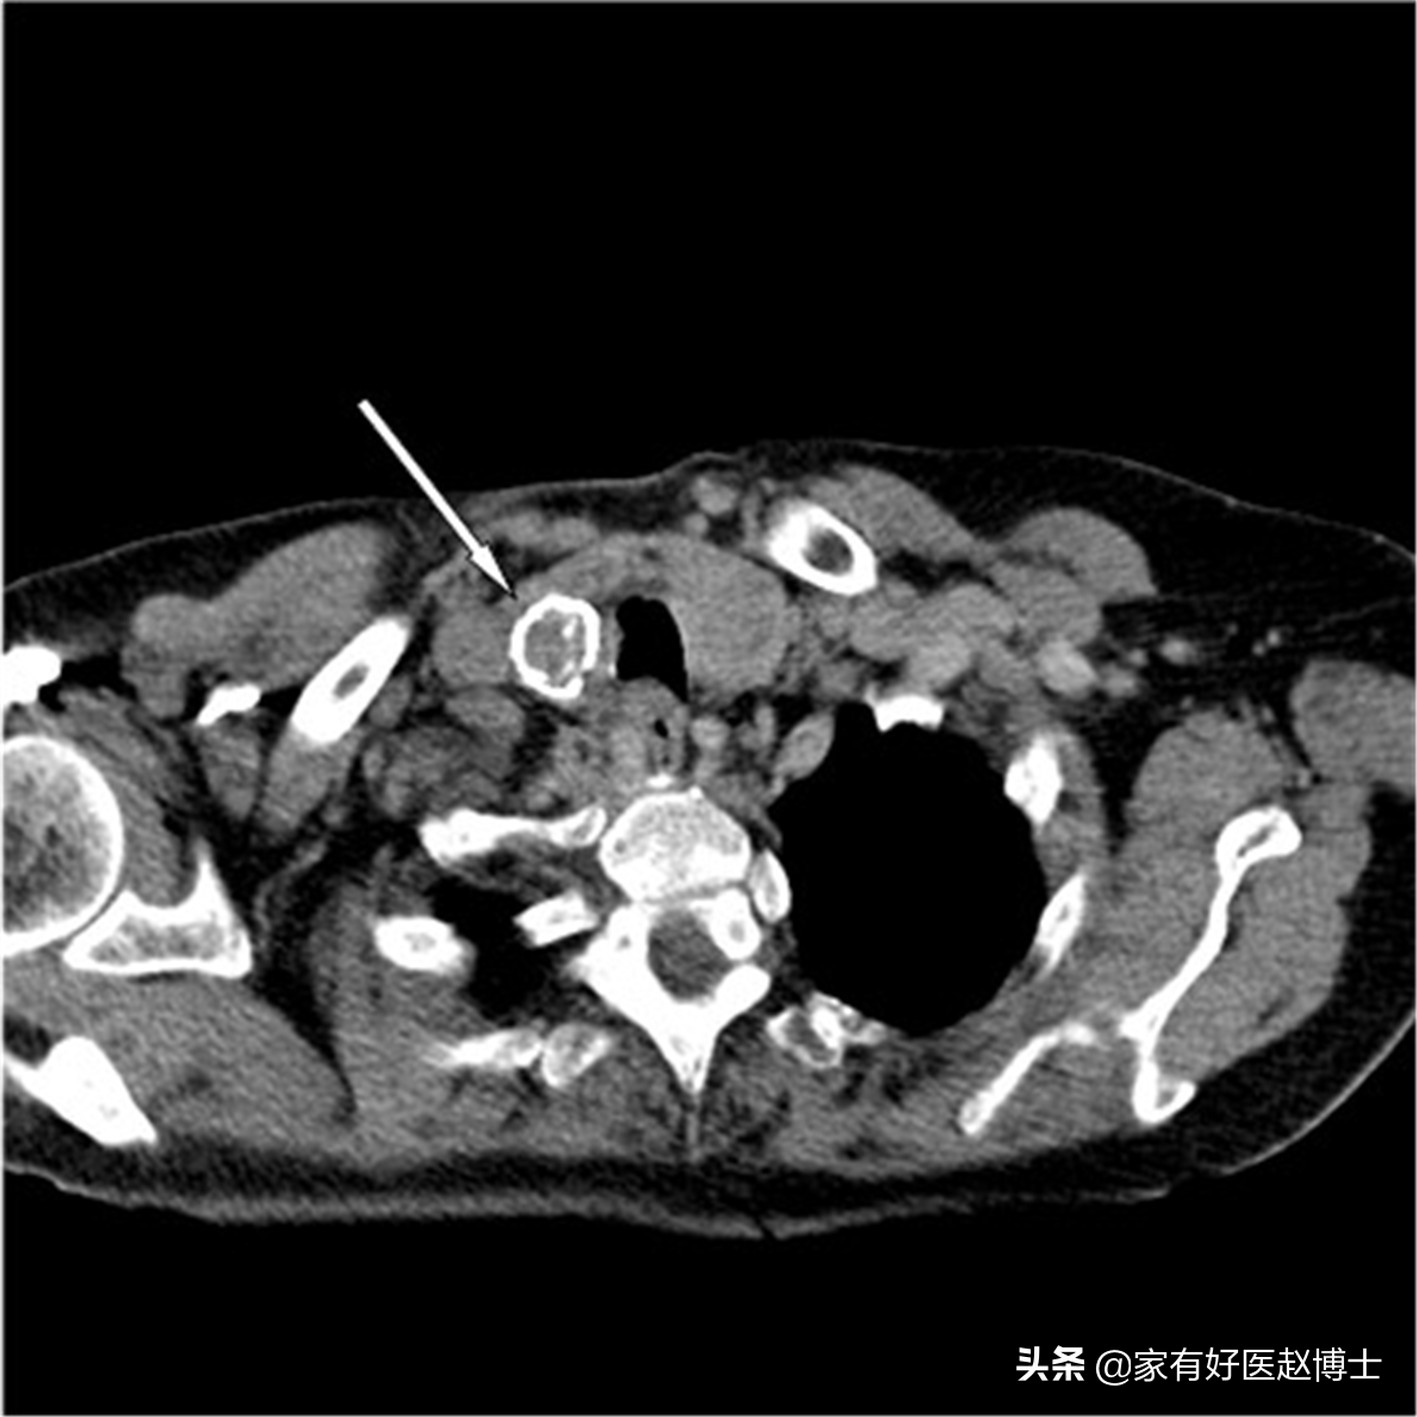

第一个要说的有恶性风险的是甲状腺里的钙化。在甲状腺疾病当中,无论是良性还是恶性的,只要能够影响甲状腺细胞的代谢状态,就都有可能引发钙化。因此,甲状腺癌、甲状腺腺瘤、结节性甲状腺肿以及桥本氏甲状腺炎等疾病都有可能引起甲状腺钙化。

甲状腺钙化常与甲状腺结节一起出现,尽管大部分的甲状腺结节都是良性的,不需要处理;但是,存在钙化的甲状腺结节则务必要引起重视,需要积极处理!

这是因为,当甲状腺结节伴随有一些特征性钙化表现时,会高度提示结节可能为恶性。比方说,微小的、针状、沙粒样钙化,常常提示恶性概率很大;而在粗大钙化以及环状钙化里,也有不低的恶性概率。

因此,当体检当中出现甲状腺钙化时,务必要引起重视,需要进一步到甲状腺外科就诊,必要时甚至可能需要穿刺检查。